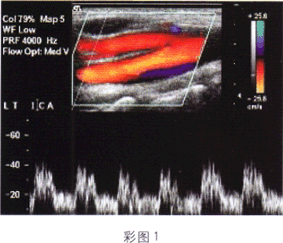

3.如图所示(彩图1),该频谱波形符合下列哪支血管的频谱特点

A.颈外动脉

B.颈内动脉

C.颈总动脉远心段

D.颈内静脉

E.椎动脉起始段

正确答案:B解题思路:颈内动脉频谱为低速低阻。